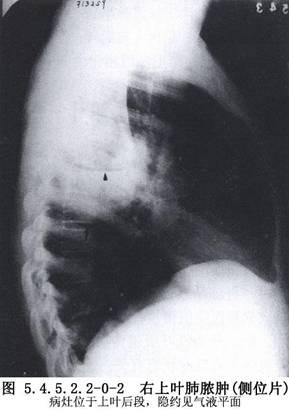

空洞是影像学上可以看到肺部有 空心部位,当肺部病变组织坏死后气体流